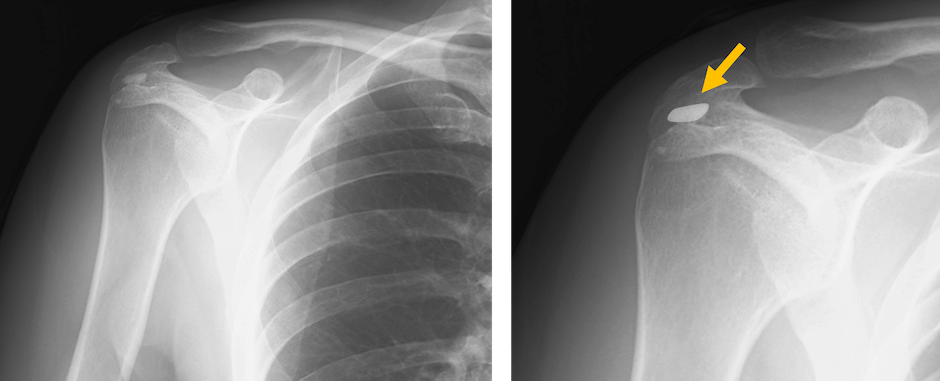

石灰沈着性腱板炎(Calcific Tendinitis)とは?

石灰沈着性腱板炎は、

肩の腱板(特に棘上筋腱)にカルシウムの結晶が沈着し、炎症を起こす疾患です。

30〜50代の女性に多く発症し、突然の強い肩の痛みが特徴です。

石灰沈着性腱板炎の特徴

- 突然の強い痛み(急性期)が特徴的で、夜間痛で目が覚めることもある

- 腱板断裂や五十肩と症状が似る場合があるが、X線で石灰沈着の有無が確認できる

石灰沈着性腱板炎の診断

- 画像検査:

- X線:腱板に石灰沈着があるか確認

- 超音波:石灰の位置や炎症の程度を評価

- MRI:腱板損傷や炎症の程度を確認

肩の腱板に石灰が沈着し炎症を起こす疾患で、急性期の強い痛みが特徴です。

X線や超音波で診断可能で、多くは保存療法で改善します。

痛みが強い場合や慢性化した場合は手術や介入療法も選択肢となります。